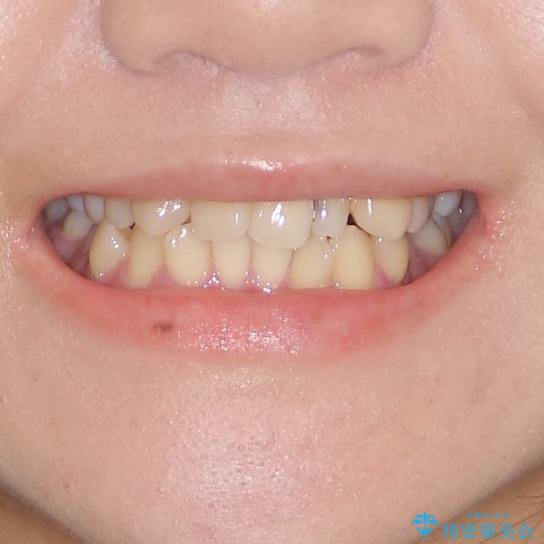

八重歯の抜歯矯正 補助装置を用いたインビザライン矯正

- 上顎の重なっている前歯を気にして来院された患者様です。

重なっている部分は抜歯が必要で、歯の移動量が多く、更には右側にずれている正中を改善する必要がありました。

インビザライン単体での治療は困難と判断し、補助装置により八重歯移動後にインビザラインを用いることとしました。

非常にしっかりとマウスピースを装着してくださいましたが、前歯の排列がなかなか仕上がらずに期間がかかってしまいました。